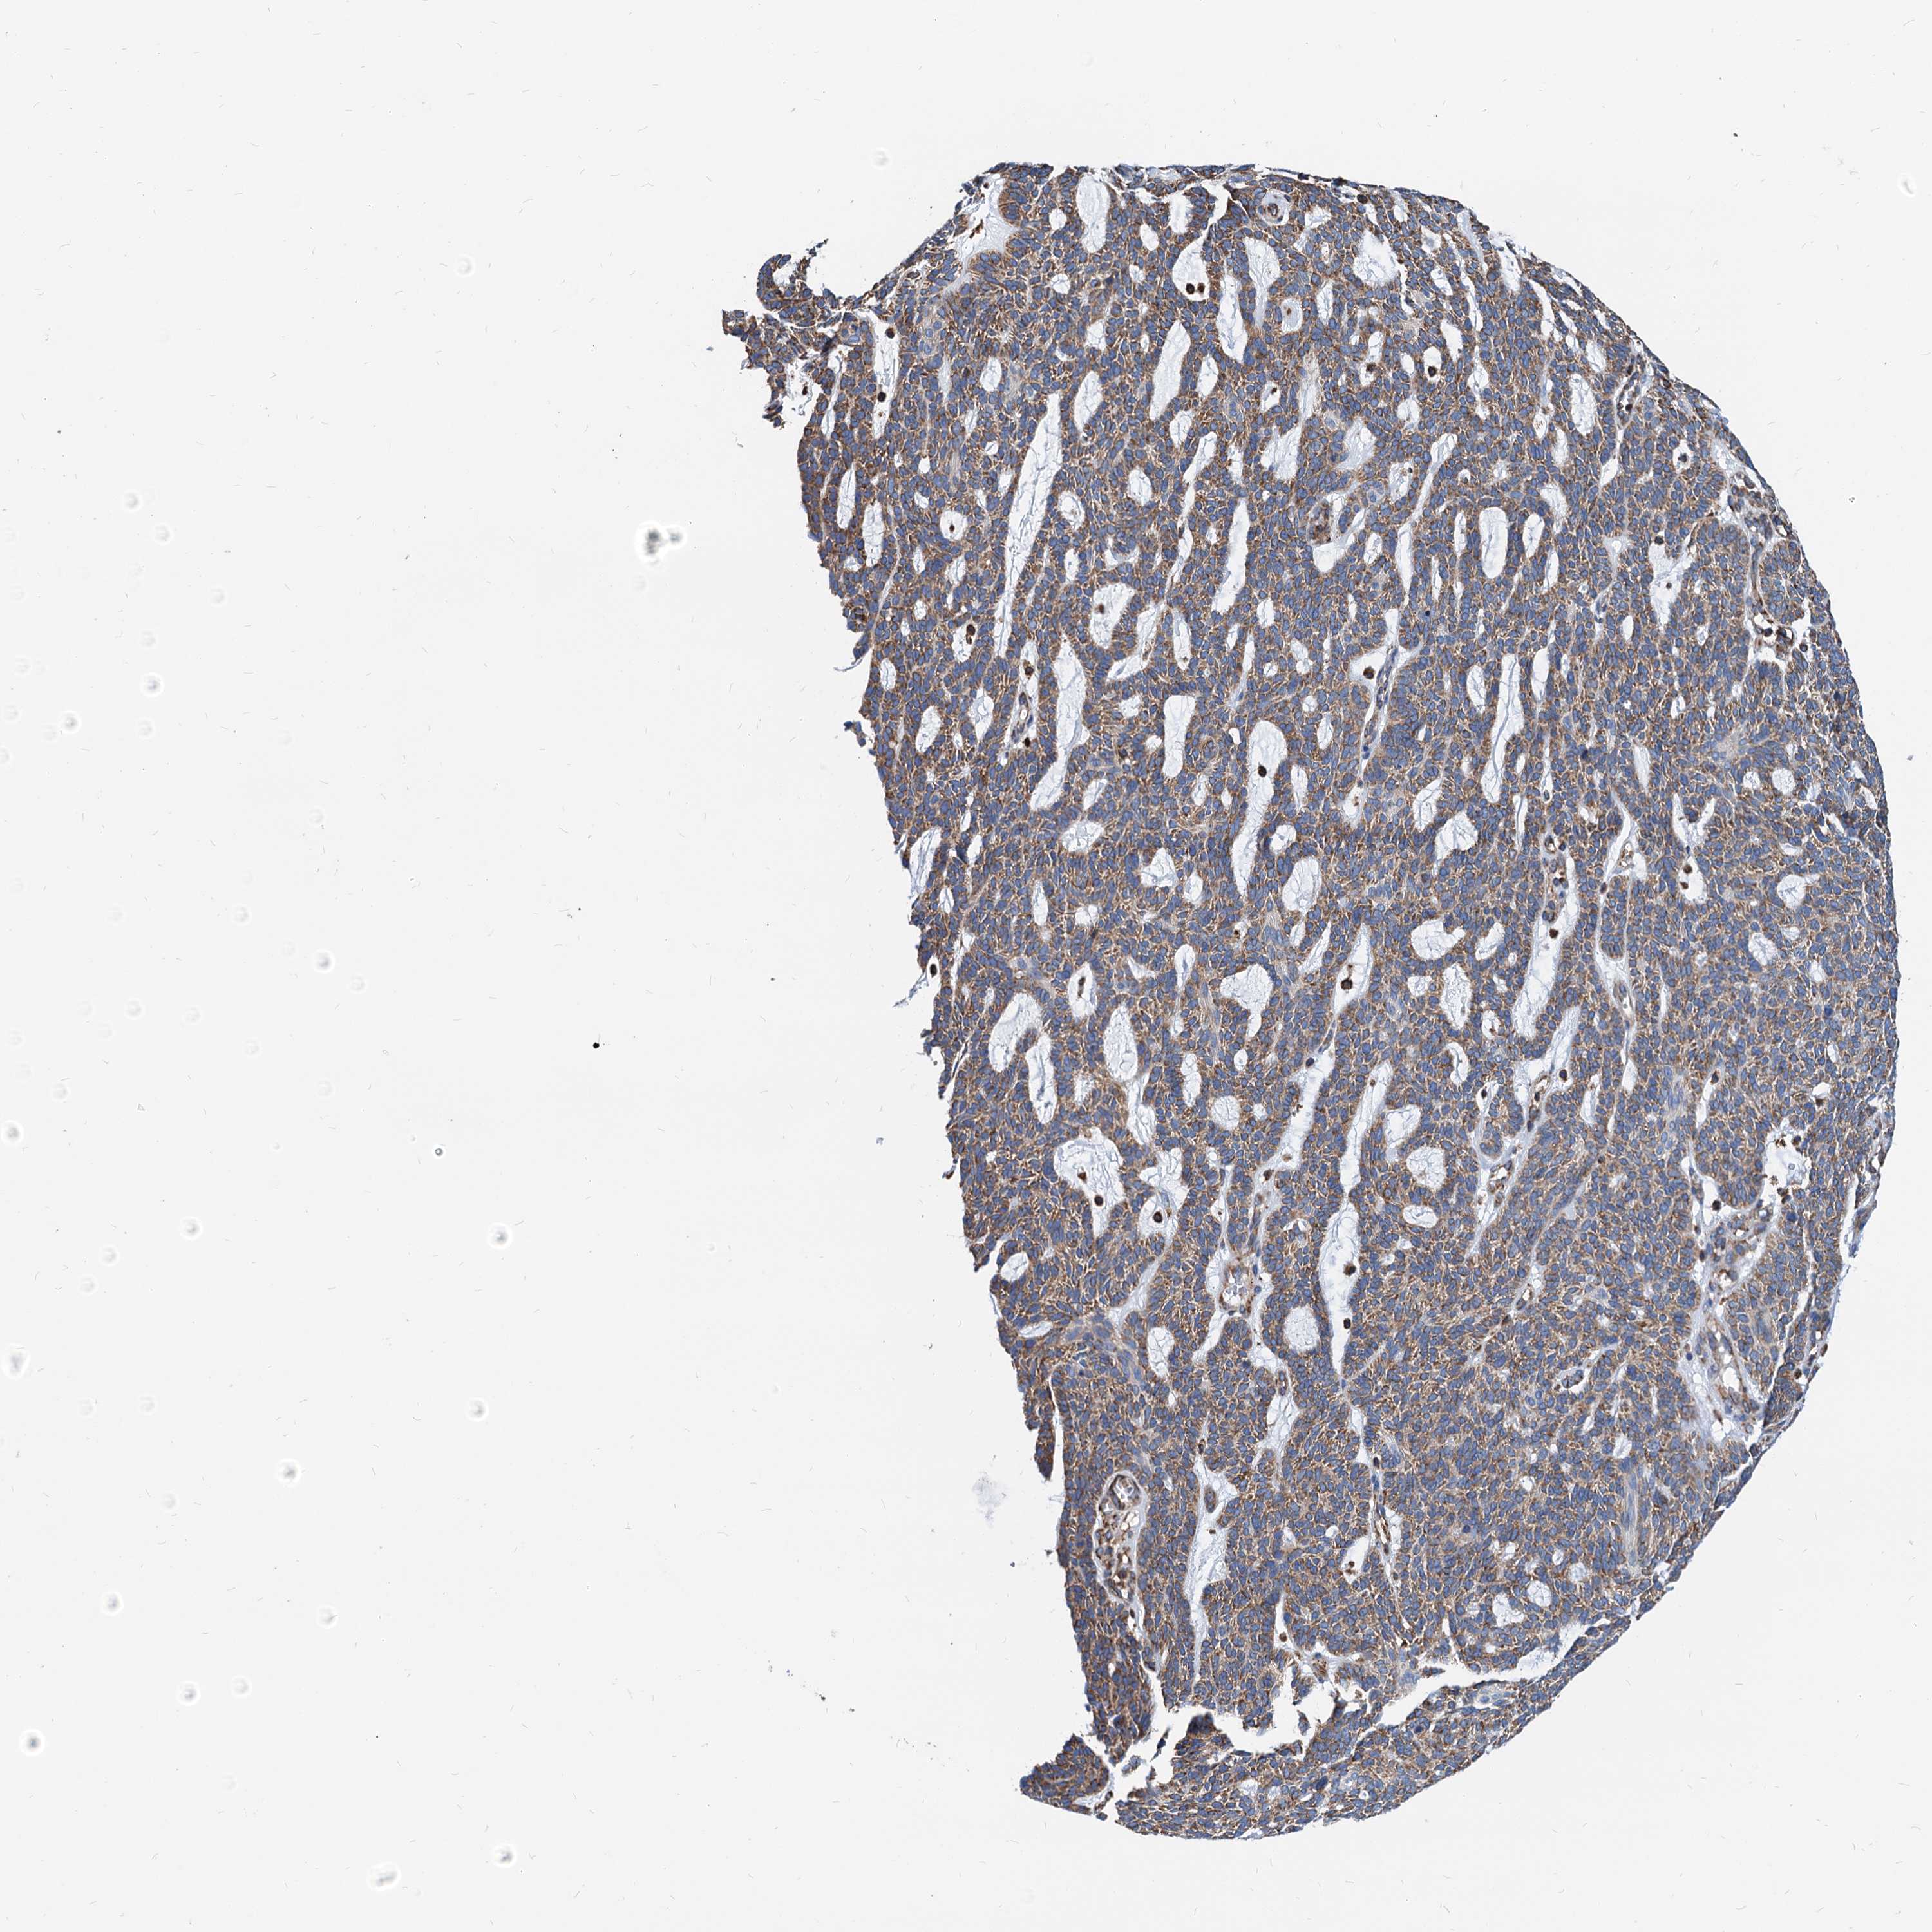

SKIN CANCER - Protein expressioni

A mouse-over function shows sample information and annotation data. Click on an image to view it in a full screen mode. Samples can be filtered based on level of antibody staining by selecting one or several of the following categories: high, medium, low and not detected. The assay and annotation is described here.

Each image is clickable and will lead to virtual microscopy that enables deeper exploration of all samples and also displays staining intensity scores, fraction scores and subcellular localization as well as patient and tissue information for each sample.

Antibody HPA038845

Antibody HPA038846

Antibody CAB005221

Staining

High

Medium

Low

Not detected

Intensity

Strong

Moderate

Weak

Negative

Quantity

>75%

75%-25%

<25%

None

Location

Nuclear

Cytoplasmic/membranous

Cytoplasmic/membranous,nuclear

Basal cell carcinoma

Squamous cell carcinoma, NOS

Squamous cell carcinoma, metastatic, NOS